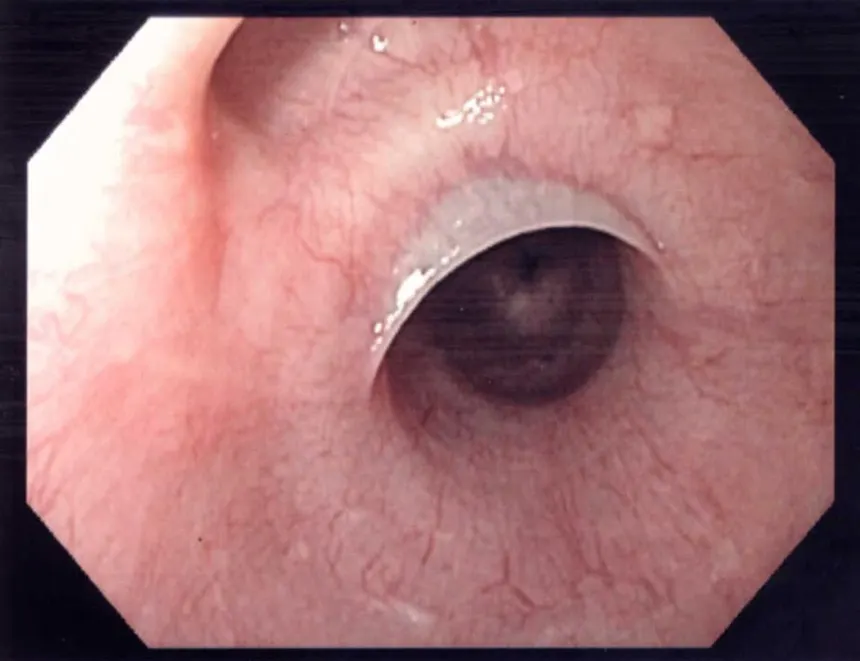

Diagnostic et aspect endoscopique

GAVE

Vaisseaux tortueux

thrombi de fibrine

saignements sévères

aspect de watermelon à l’endoscopie